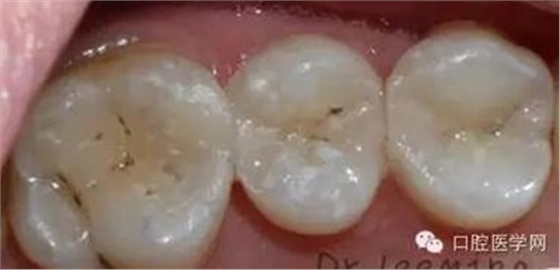

這個(gè)患者是我的小粉絲,女兒大部分的齲齒都是我處理好的,家長(zhǎng)很滿意。這次媽媽終于有時(shí)間來(lái)看牙齒,昨天充填了三顆二類(lèi)洞,術(shù)后照片看,對(duì)于第一磨牙最后的充填效果,狠狠的給自己的熱情潑了冷水,第一磨牙窩溝上的齲是沒(méi)有處理的,有些覆蓋在上面的樹(shù)脂,是因?yàn)樗苄蔚臅r(shí)候,把樹(shù)脂推過(guò)去的,術(shù)后只是調(diào)磨了一下咬合高點(diǎn),沒(méi)有精修和拋光,也打算復(fù)診回來(lái),看看第一磨牙的情況,再選擇重新的充填,然后整體精修拋光。